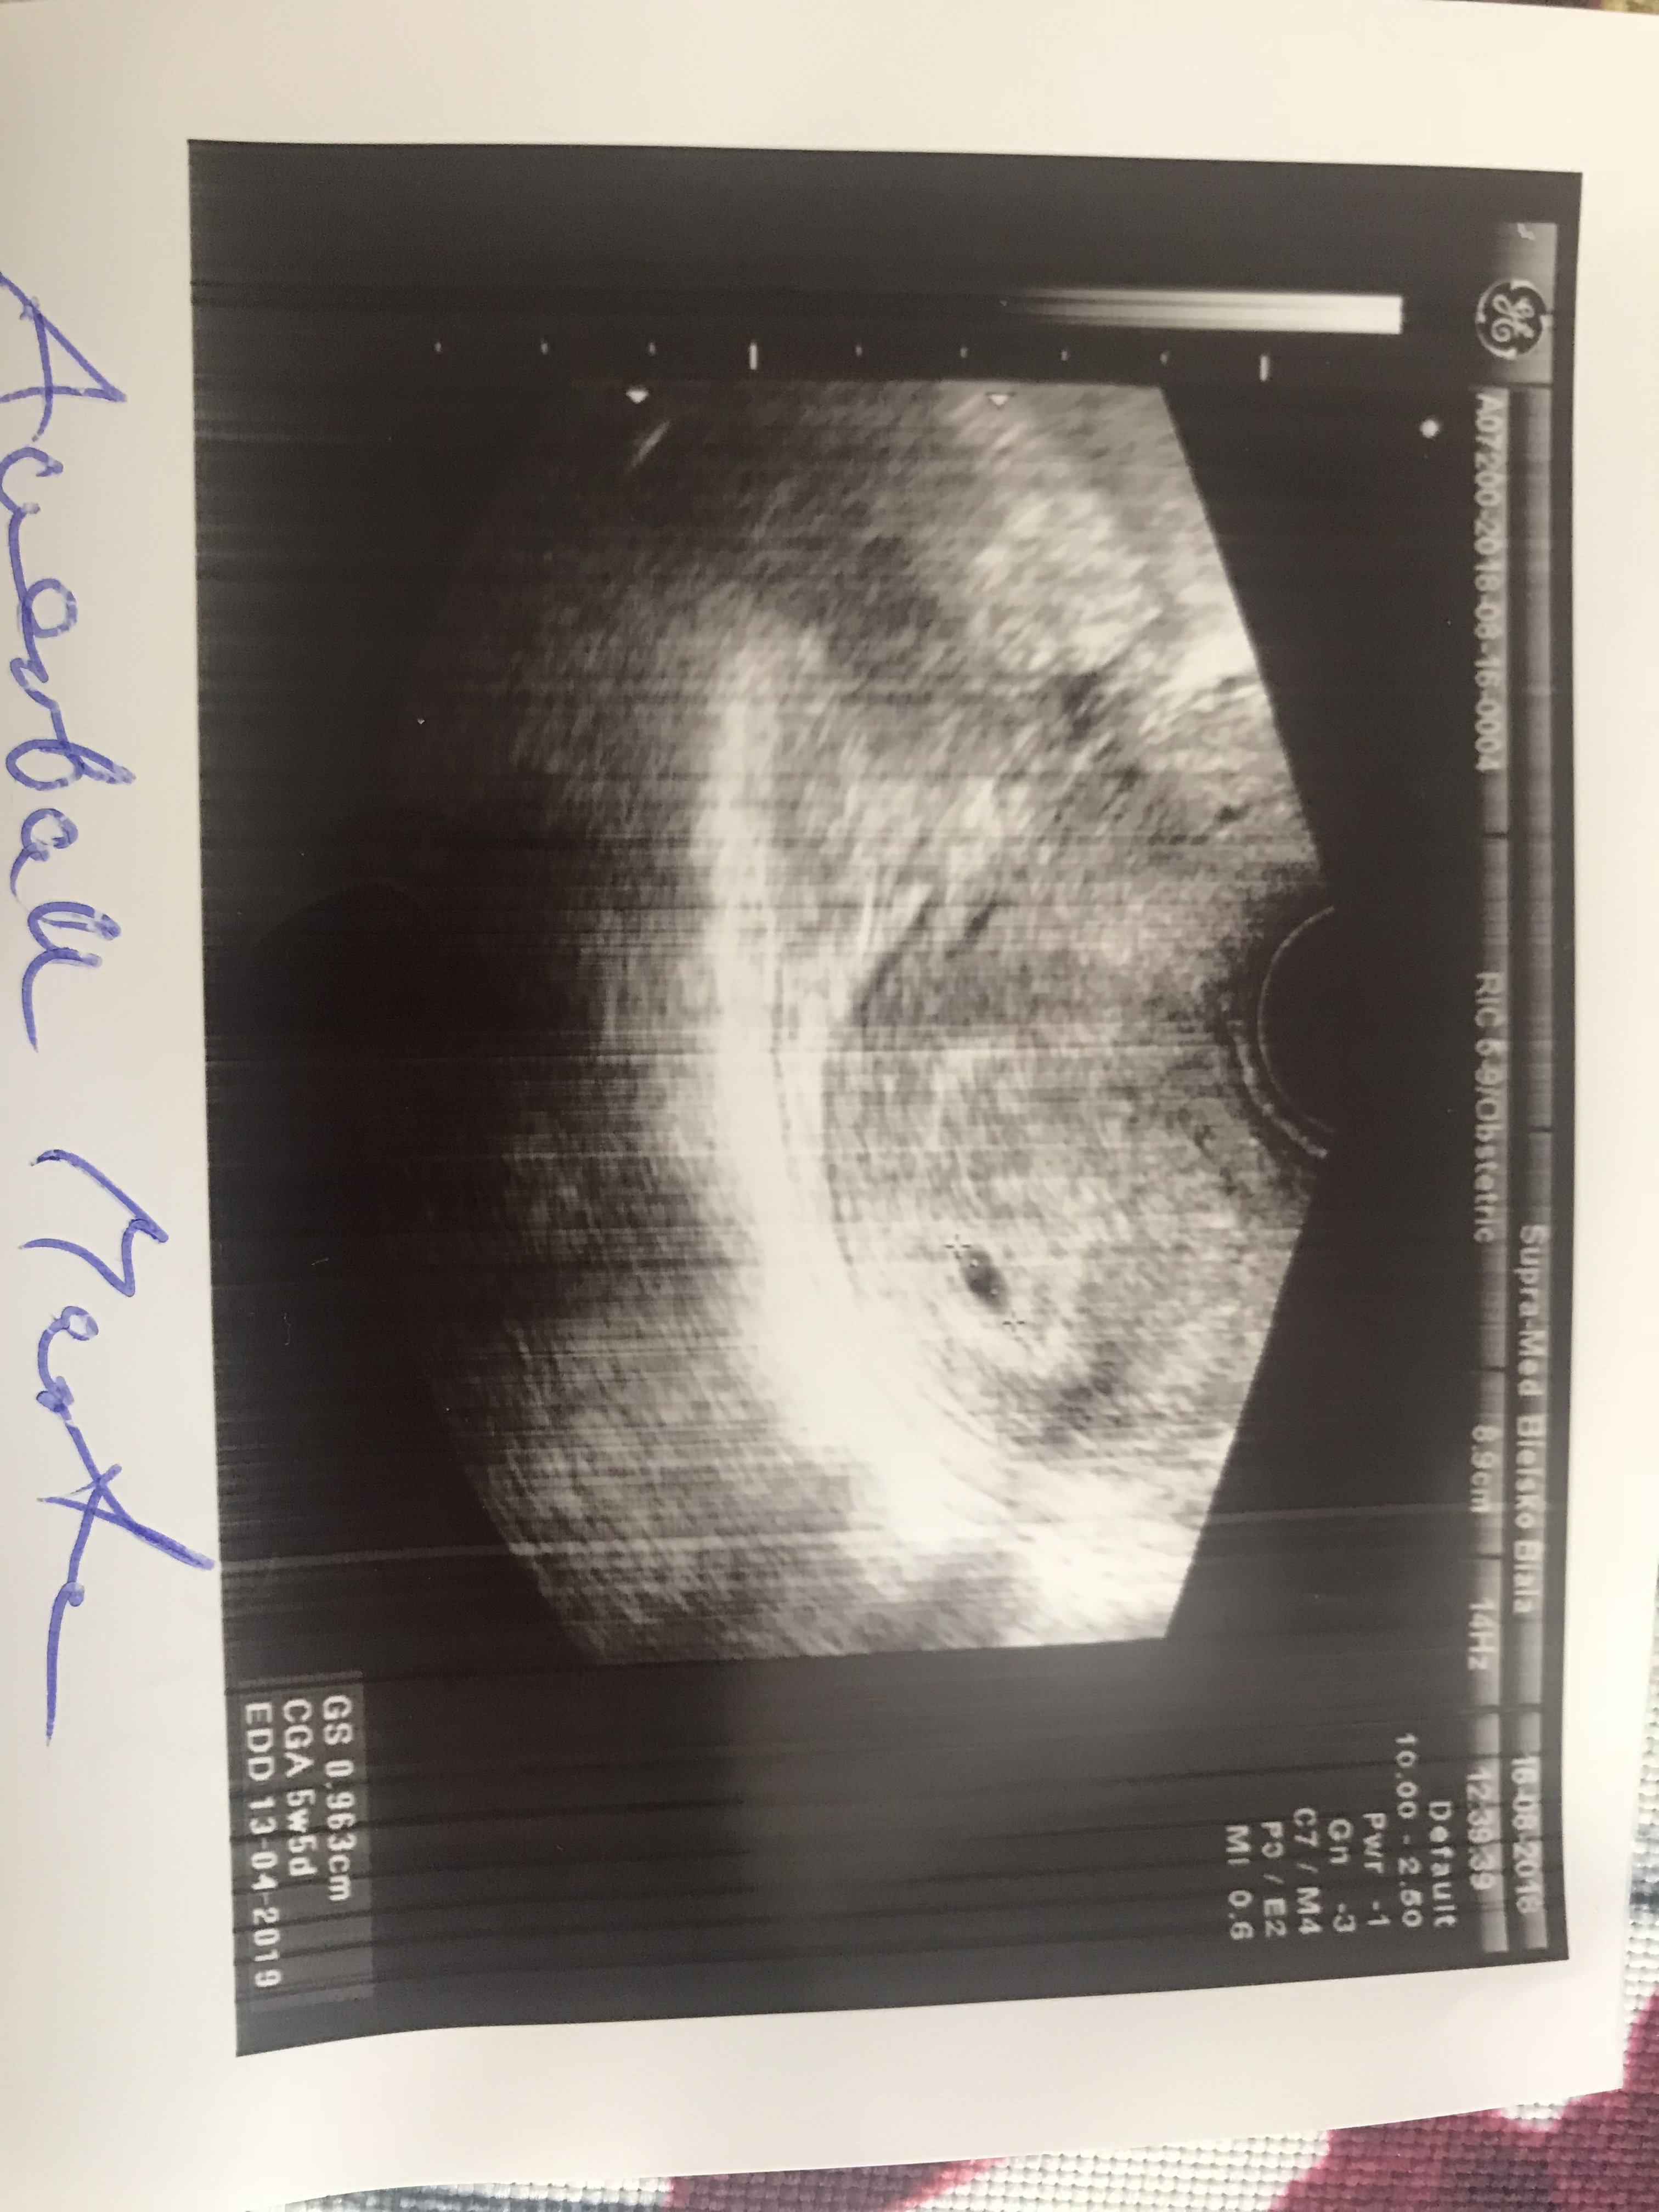

Hejka witam wszystkich, ja już po 1 wizycie jest pęcherzyk, 5w5d następna wizyta za 2,5 tyg i czekam na![]()

także po wizycie, serduszko pieknie bije. Z OM 7 tydzien 1 dzień. Termin na 4 kwietnia